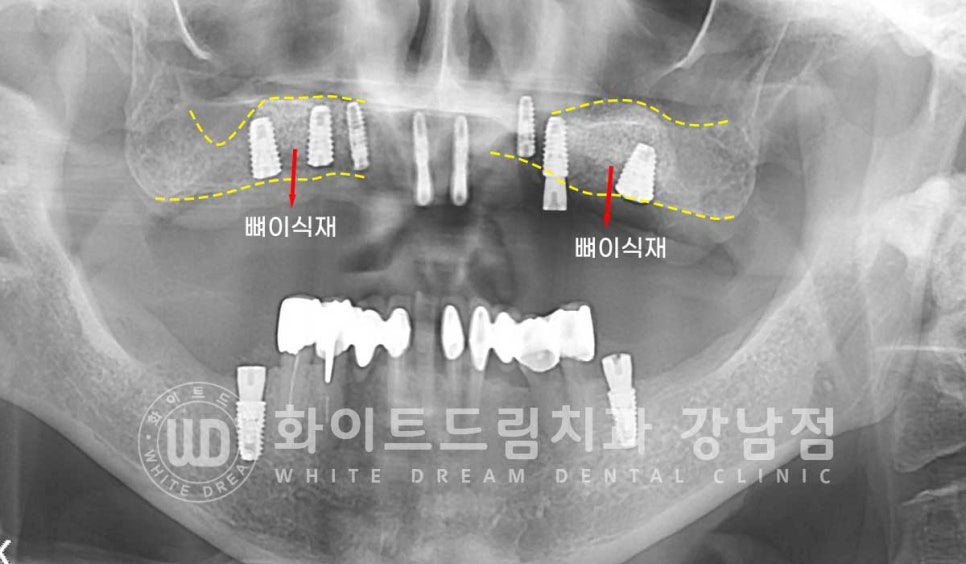

많은 양의 뼈이식이 들어갔고 초기 골소실이 심했던 부위이기에

1차 수술과 2차 수술을 나누어 진행했고

잇몸뼈의 골폭이 좁은 전치부는 직경 3.5mm의 미니 임플란트를 식립하고

어금니 부위는 직경 6mm의 와이드형 임플란트를 이용하여

고정력과 안정성을 높였습니다.

환자분처럼 6mm의 두꺼운 임플란트는 잘 사용하지는 않으나

초기 골 소실이 심해 고정력이 약한 경우는 직경이 넓은 임플란트를 선택하여

잇몸뼈와 접촉면적을 넓혀 고정력과 안정성을 높여주는 것도 하나의 좋은 선택이 될 수 있답니다.